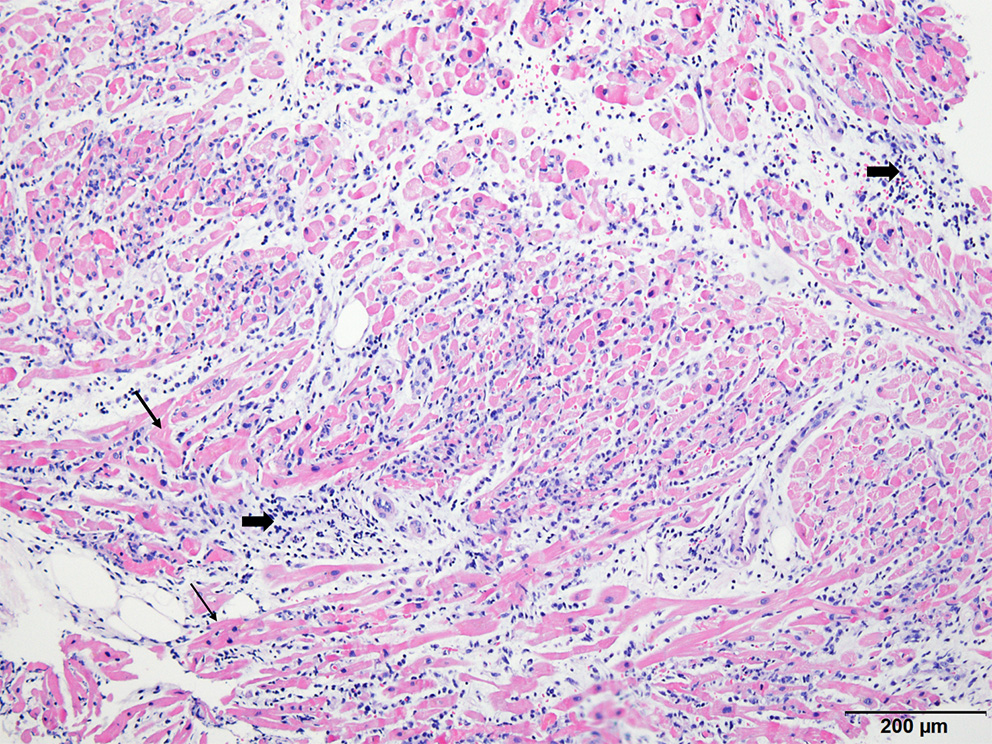

Figure 3

Histopathologic examination of endomyocardial biopsy revealed marked and diffused infiltration of lymphocytes (thick arrow) within the myocardium (thin arrow) (×40, Hematoxylin-eosin stain).

On the third hospital day, echocardiography showed more improvement in both the ventricular function (ejection fraction: 30%) and the decreasing thickness of the LV wall (10 mm). In addition, the ECG showed a more decreased ST segment elevation with the narrowing of QRS complexes (Figure 1C). The patient was extubated on the same day, and ECMO weaning was done on the sixth day. EMB demonstrated compatible findings of acute lymphocytic myocarditis (Figure 3).

In the present case, the diagnosis of myocarditis was confirmed by histology. EMB is a golden standard for the diagnosis of fulminant myocarditis and is highly recommended by expert consensus for clinical purposes (21, 22). It can be seen in cases, reports of post-COVID-19 vaccination myocarditis in the literature that endomyocardial biopsy has been performed in a few cases (13, 14, 23, 24). This lower rate of EMB might be either due to the benign nature of the post-COVID-19 vaccination myocarditis itself, or regional preference of clinical practice for myocarditis. In the COVID-19 era where there are continuous requirements for vaccination for the infection, confirmation of diagnosis by EMB should be more essential for both clinical and research purposes, regardless of reasons for the lower EMB rate. The mechanism of myocarditis following mRNA COVID-19 vaccination, indeed, has not been elucidated and it could be attributable to its relatively rare incidence and benign course. All the factors could contribute toward the lower rate of EMB or autopsy, which produces samples for research.